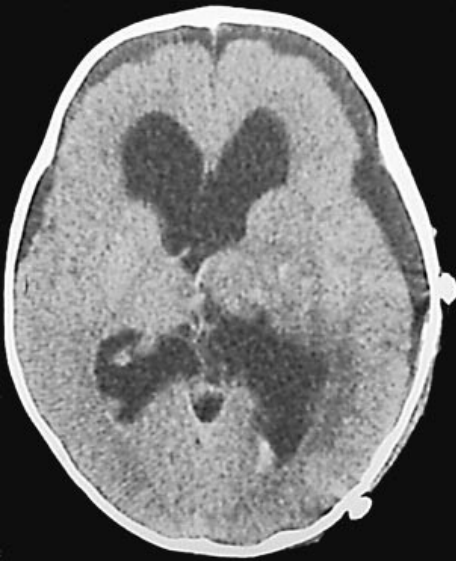

Di Rocco教授曾接诊过一名4个月大的女婴,父母发现她的头颅异常增大,一检查才发现,一个巨大的脉络丛乳头状瘤,位于第三脑室,并延伸到了侧脑室。经囟门超声和脑磁振造影证实,在伴有继发性梗阻性脑积水的第三脑室和侧脑室确实存在肿块。

颅脑MR显示侧脑室及第三脑室内的脉络膜丛乳头状瘤